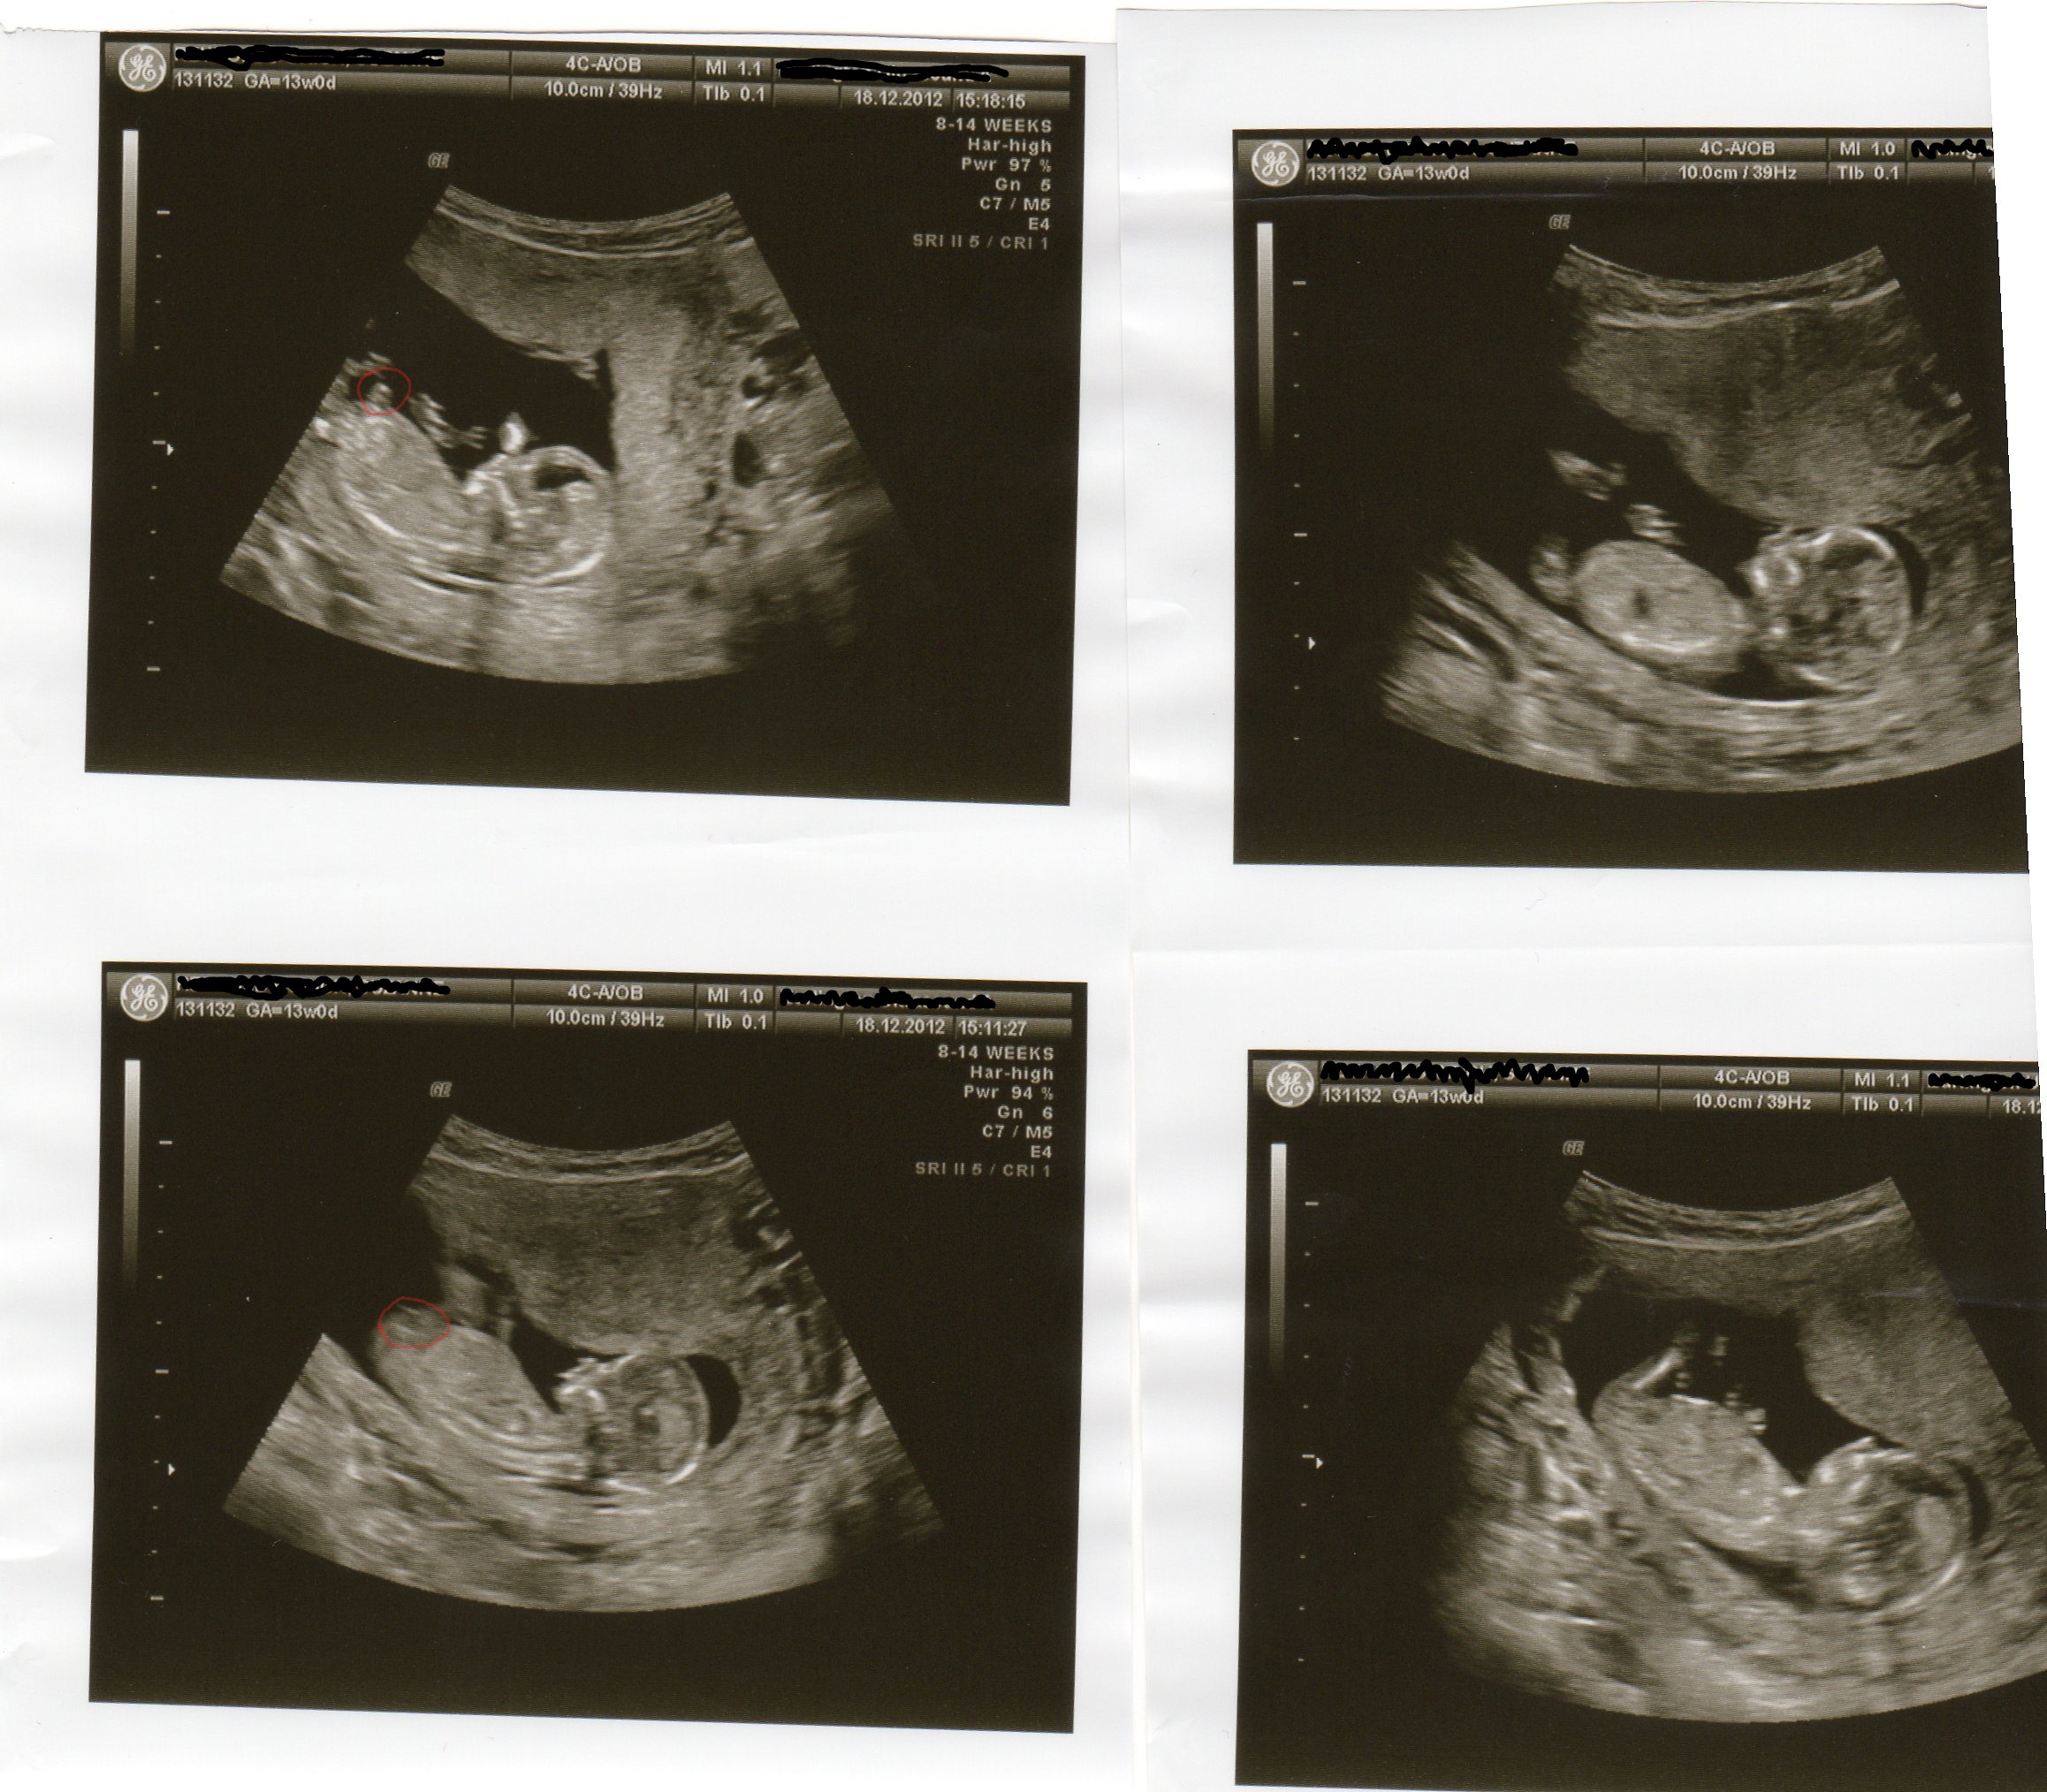

Attachment 7648

Ok hope you don't mind but i blew the others up to, whilst i was sticking my nose in, just in case it helps you get any more guesses :happy:

Attachment 7649

Attachment 7650

Attachment 7651